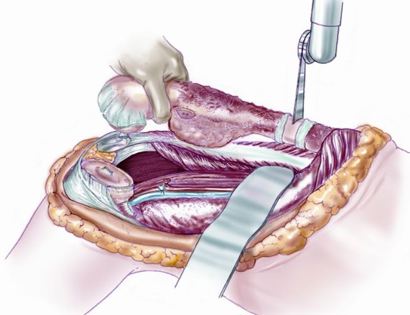

Intra-Op: Soft Tissue Coverage

After the prosthesis is inserted into the femur bone, muscle is used to attach and cover the prosthesis to ensure proper functioning post-surgically.